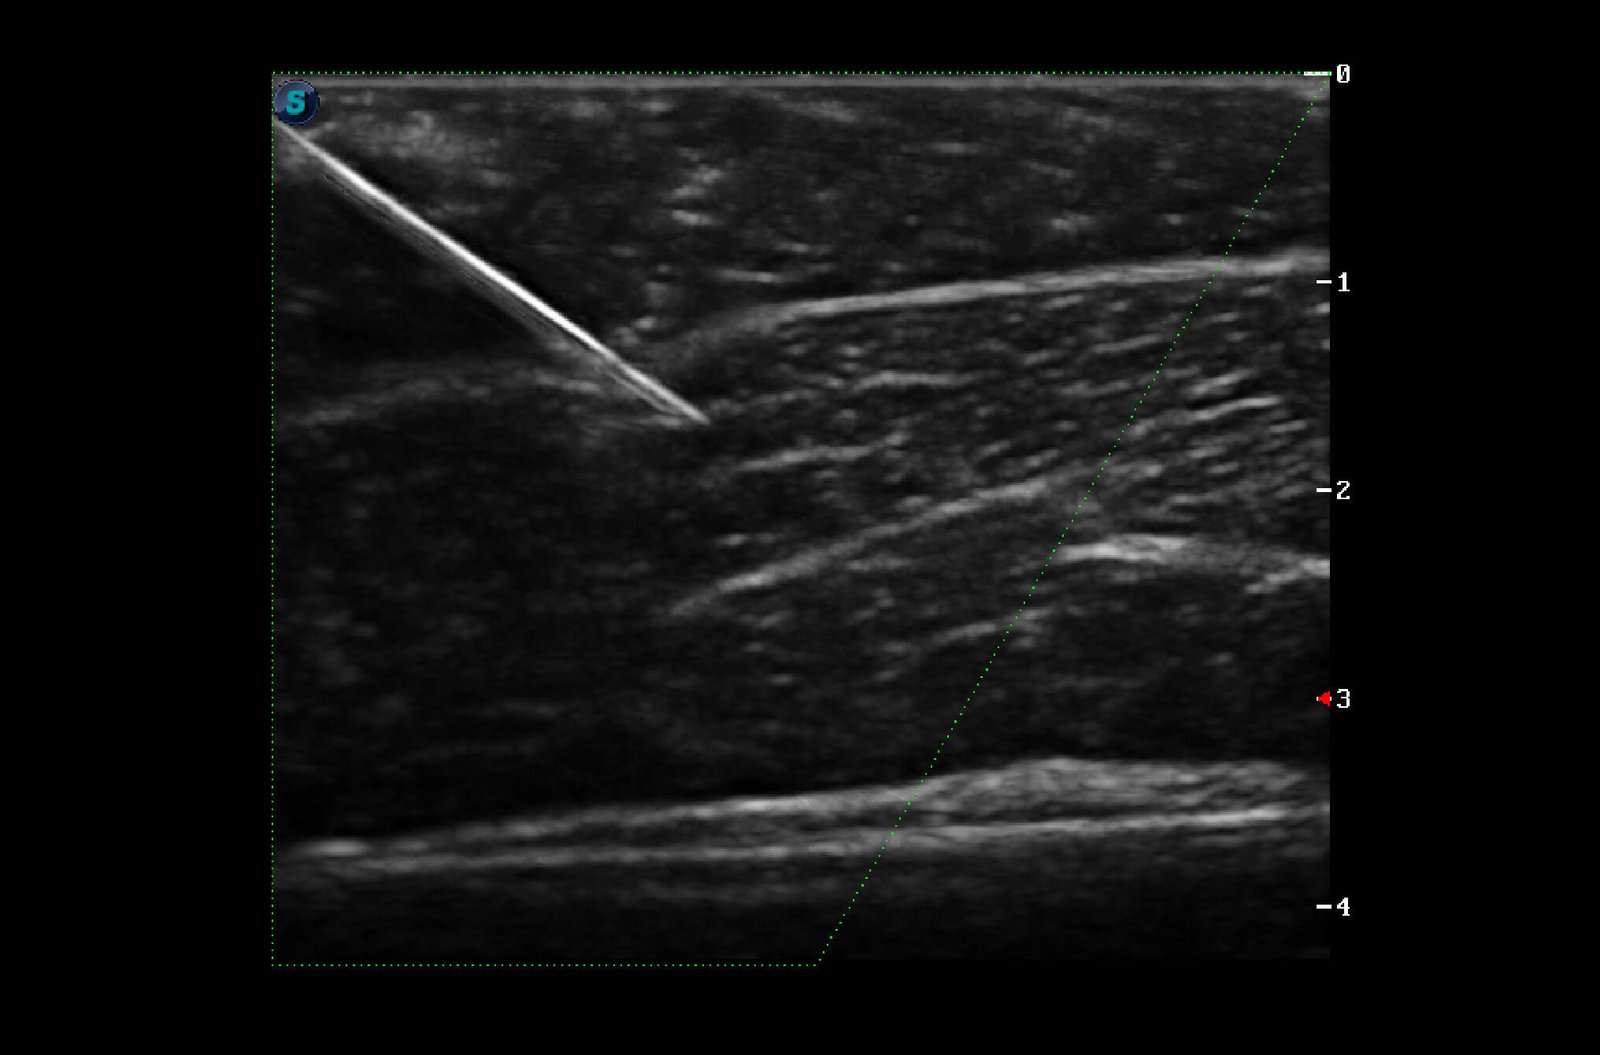

Composite Crystal Linear Transducers

Better acoustic spectrum and lower acoustic impedance technology serve well in vascular, breast, thyroid, MSK, etc. The combo of 12L-A, 12L-B, 9L-A covers an ultra-wide frequency bandwidth, leaving nearly no blind spot for all sorts of scanning.